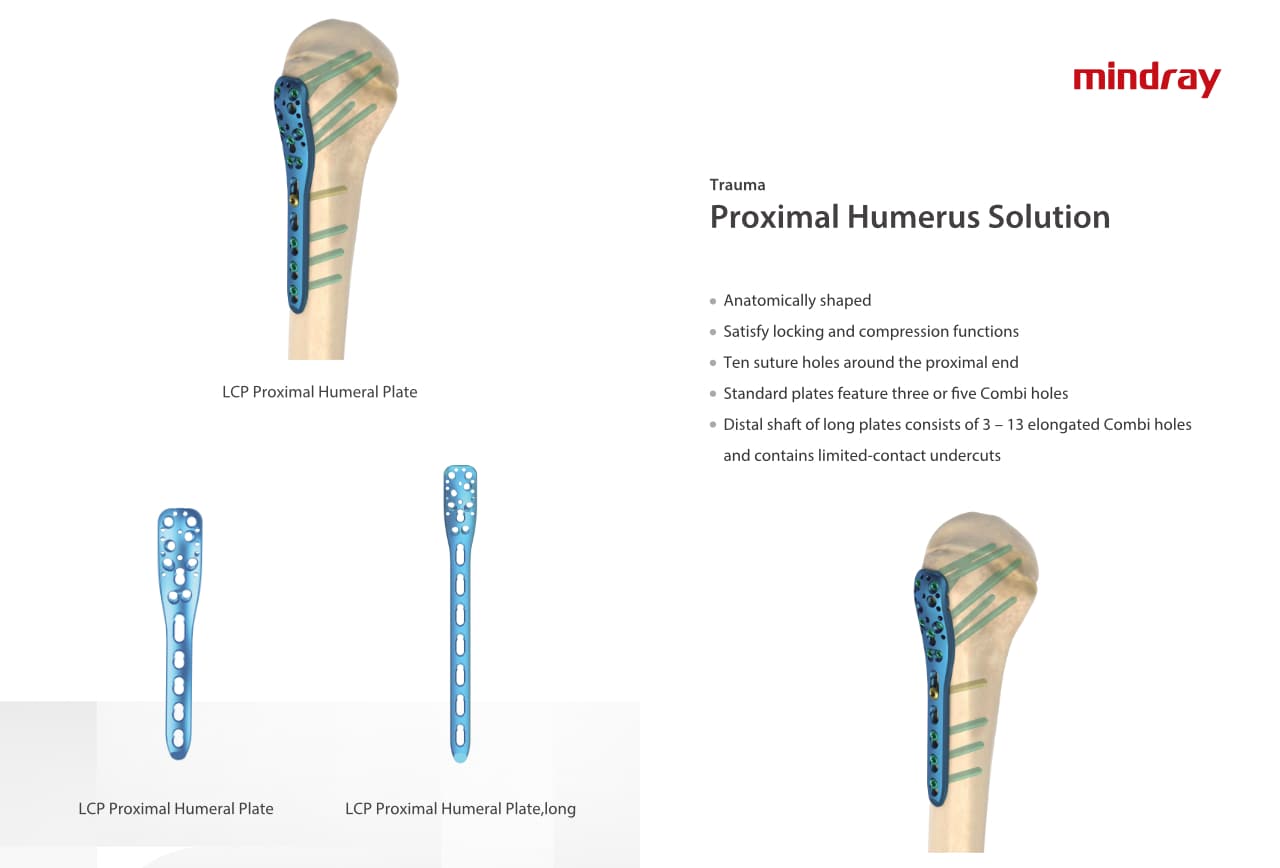

Trauma